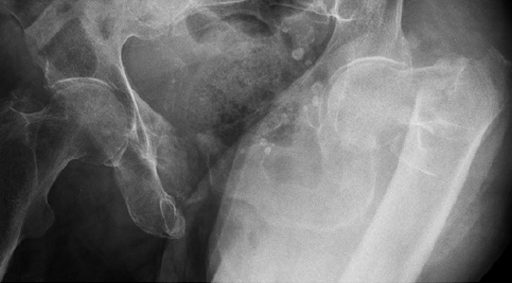

An 82-year-old woman with an unstable pertrochanteric fracture of the right proximal femur. Her Barthel Index was 80 and her preoperative Parker mobility score was 5, which means that she was walking at home unassisted. The patient's preoperative Parker mobility score of 5 was reached again at the 3-month follow-up.